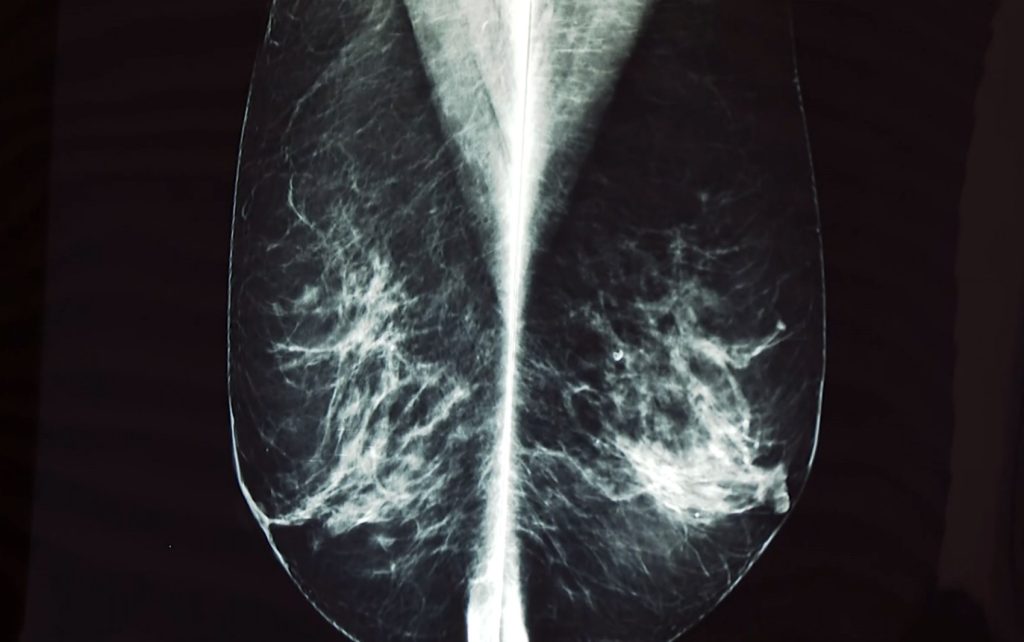

“Para eu fazer esse ultrassom de seis em seis meses, praticamente eu paguei todos eles, porque fiquei esperando pelo SUS, não saía. Aí o médico perguntou porque eu não tinha levado o resultado do ultrassom, foi assim que a secretaria não tinha mandado, ele fez na hora. E tinha crescido um pouco o nódulo. Ele falou que eu tenho que manter de seis em seis meses. Só que eu já tenho dois anos que estou esperando”, disse.